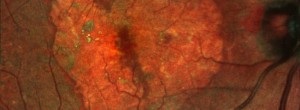

Fase III Estudio de Lampalizumab en pacientes con atrofia geográfica secundaria a DMAE

MPL4 GA: Estudio Fase I en pacientes con atrofia geográfica secundaria a DMAE atrófica

Oral Omega 3 GA. Estudio Fase II para pacientes con atrofia geográfica secundaria a DMAE

Reappraisal of geographic atrophy patterns seen on fundus autofluorescence using a latent class analysis approach.